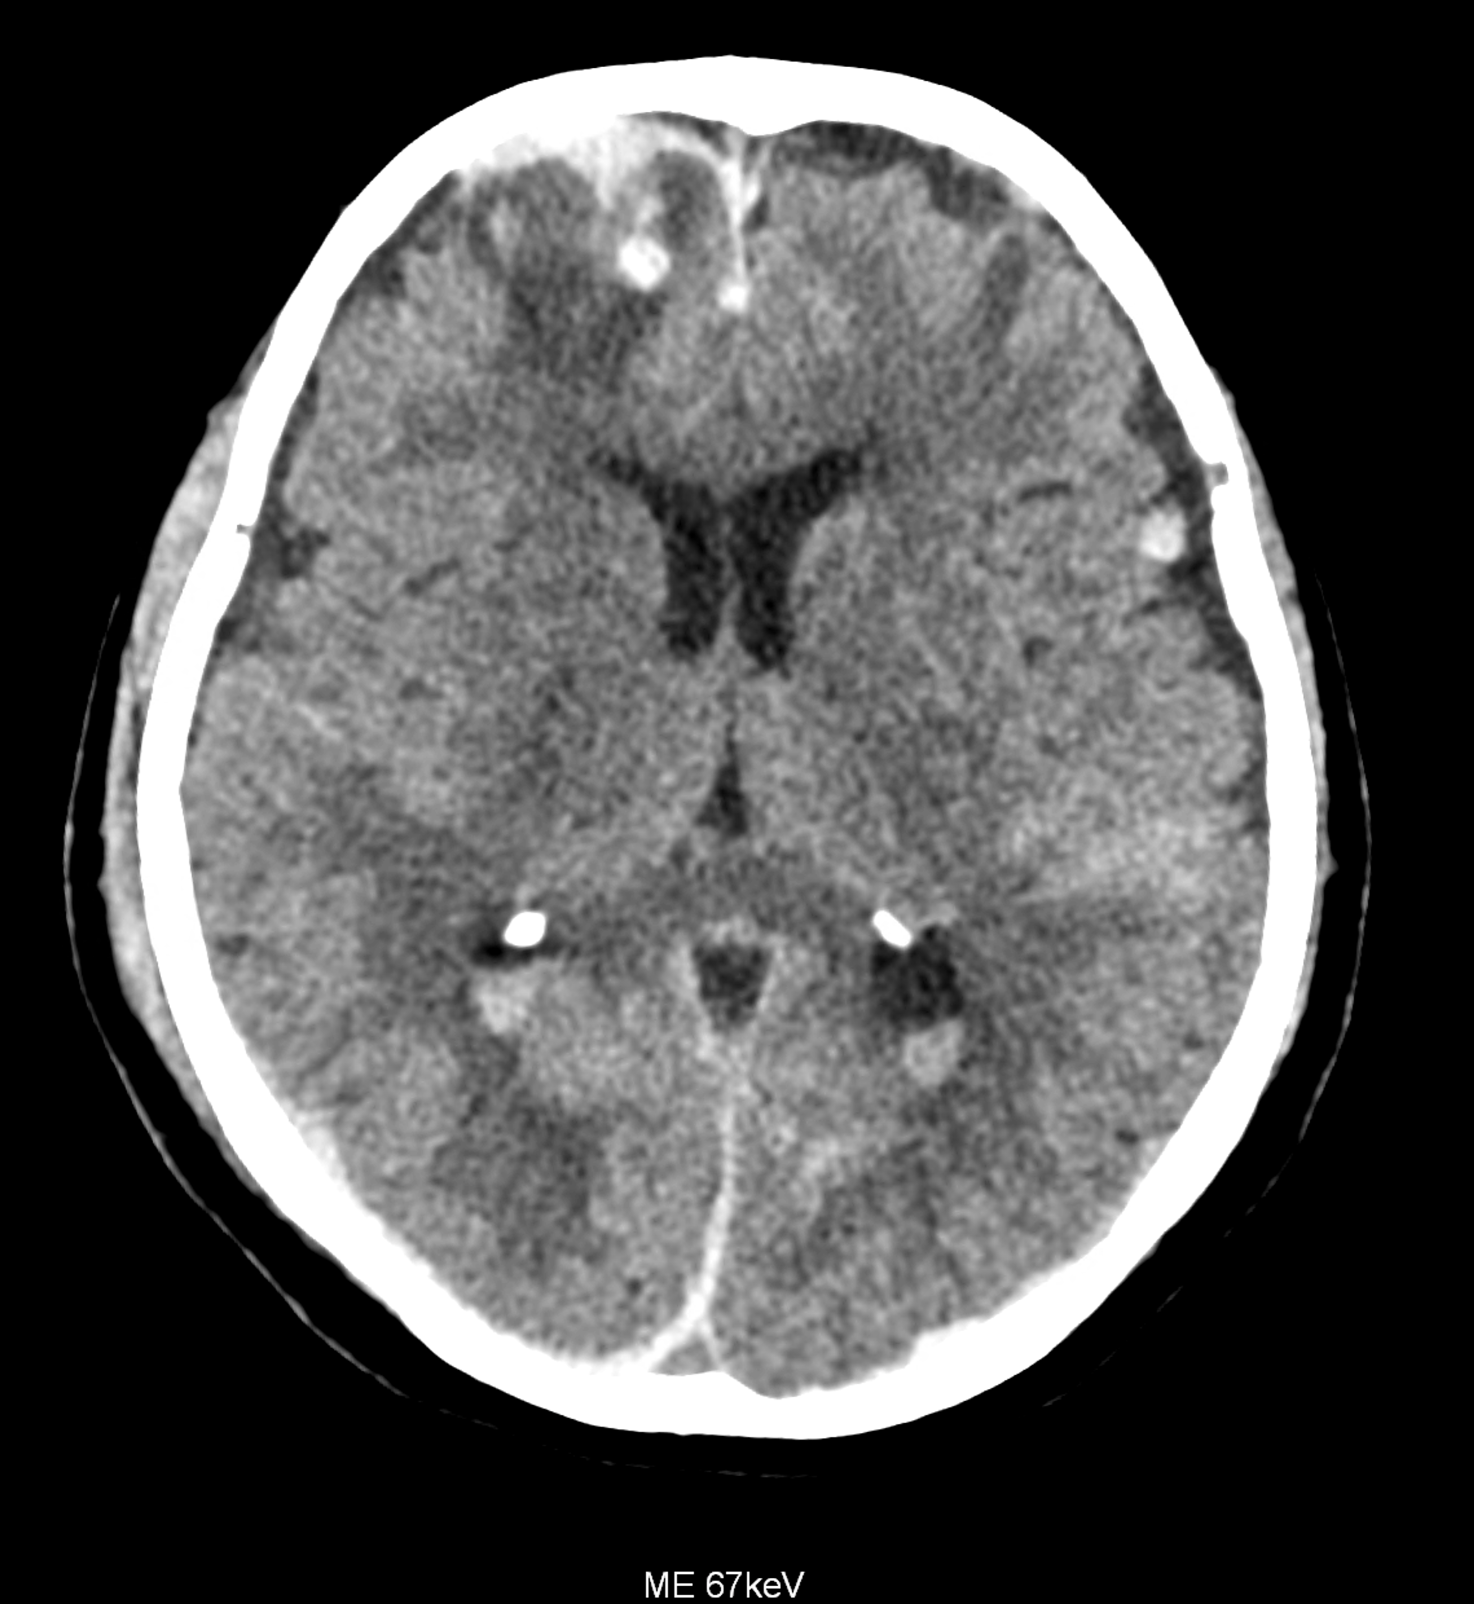

An example of the use of spectral imaging in complex brain injury, where contusions, diffuse axonal injury, subarachnoid hemorrhage, subdural hemorrhage, and blood in the ventricular system are present.

comparison of the images with the energies of monoenergetic reconstructions 40 keV, 67 keV (standard conventional reconstruction), 190 keV and virtual non contrast (VNC)